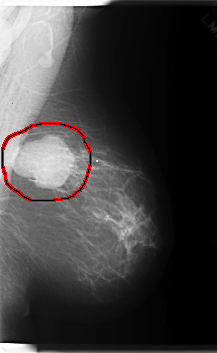

C_0219_1.RIGHT_MLO

LEFT_CC LINES 6000 PIXELS_PER_LINE 3480 BITS_PER_PIXEL 12 RESOLUTION 50 OVERLAY

FILE: C_0219_1.LEFT_CC.OVERLAY

TOTAL_ABNORMALITIES 1

ABNORMALITY 1

LESION_TYPE MASS SHAPE OVAL MARGINS CIRCUMSCRIBED

ASSESSMENT 5

SUBTLETY 5

PATHOLOGY MALIGNANT

TOTAL_OUTLINES 1

BOUNDARY